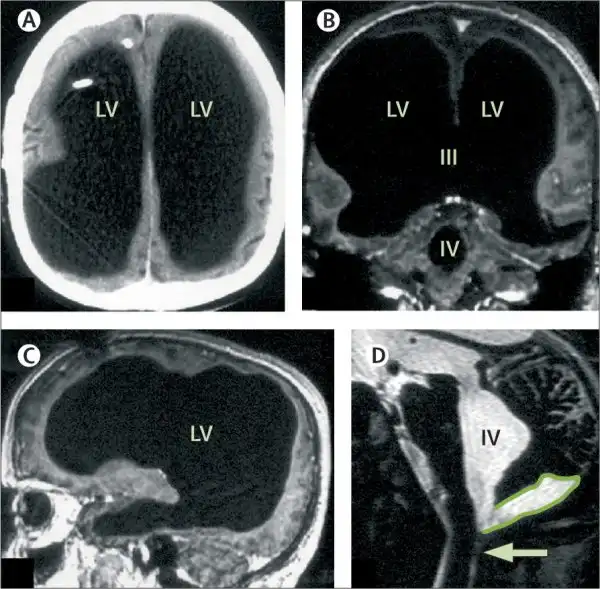

Магнитно-резонансная томограмма пациента с практически отсутствующим мозгом, но ведущим нормальную социальную жизнь.

Сканирование мозга мужчине сделали практически случайно. Он пришёл в больницу с жалобой на слабость в левой ноге, но врач направил его на томограмму. Результаты МРТ показали, что череп мужчины практически полностью заполнен жидкостью. Остался только тонкий внешний слой с мозговым веществом, а внутренняя часть мозга практически отсутствует.

На иллюстрации слева показана томограмма мозга пациента, у которого большая часть черепа заполнена жидкостью. Для сравнения, на томограмме справа — через обычного мозга без аномалий.

Учёные считают, что мозг пациента медленно уничтожался в течение 30 лет по мере накопления жидкости — процесс, известный как гидроцефалия (водянка головного мозга). Ему поставили такой диагноз ещё в подростковом возрасте и провели шунтирование для восстановления движения ликворной жидкости, но в 14 лет шунт убрали. С тех пор жидкость в черепе накапливалась, а мозг постепенно уничтожался.